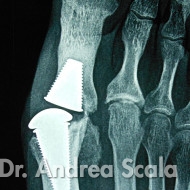

Alluce rigido operato con protesi fallita

IMG 4 – La radiografia mostra che il tentativo di impiantare una protesi per alluce rigido non ha ottenuto il movimento desiderato. La protesi si è bloccata, le componenti si sono spostate.